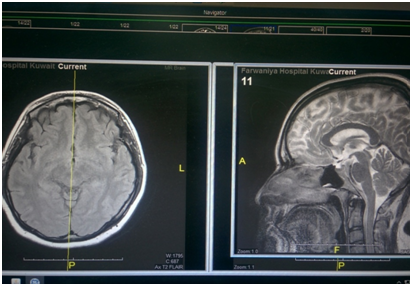

A 28 years old female patient, who was 27 weeks pregnant, had a syncope followed by noticing vertical binocular diplopia. On examination, the patient had impaired elevation which was asymmetrical being more on obvious on the right side, retraction nystagmus, and pupillary light-near dissociation in both eyes. Otherwise no other focal neurological deficits were detected. MRI and MRV showed no abnormalities. While an MRI with contrast revealed a focus measuring 4X8mm of altered MRI signal at the superior para-sagittal region in the right half of the midbrain. (tegmentum) just below the thalamus with no perifocal edema or mass effect, denoting being ischemic in nature. All blood tests were within normal limits, and her coagulation profile was within normal limits (Table 1). The cause of that ischemic lesion couldn’t be identified, but a planned CTA will be carried out after her delivery (as an elective c-section) to identify any vascular abnormalities. Until then, the patient is kept on oral aspirin (Figures 1 & 2).

Figure 1 MRI T2 axial and sgittal sections showed no anomalies in the midbrain region.

Figure 2 MRI T2 axial and sagittal sections with contrast showed the lesion in the midbrain.